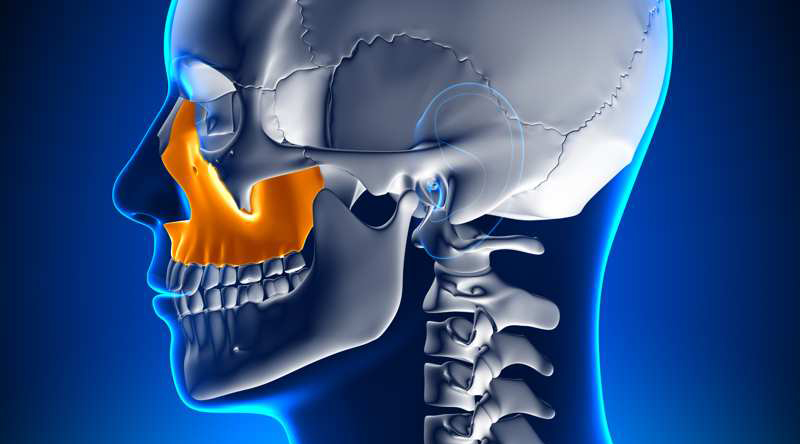

Ambos procedimientos se aplican al maxilar superior. En muchos pacientes observamos un hueso notablemente blando y/o incluso hueco. Esta combinación de hueso blando y hueco provoca que los implantes convencionales no sean fuertes y seguros, y debemos hacer algo para aumentar esa fuerza y poder colocar implantes dentales. Mediante una exploración 3D detectamos aquellos pacientes faltos de hueso. En este momento es cuando aparecen las dos opciones: reconstruir o injertar hueso, o colocar implantes en el pómulo, los conocidos como cigomáticos.

Habitualmente nos decantamos por el implante cigomático cuando es necesario reemplazar el conjunto completo de los dientes superiores. Esto permite que todos los dientes se conecten en forma de arco, aportando la fuerza y la rigidez en un sistema donde cada implante se fortalece como una pieza natural, además se trata de un procedimiento de carga inmediata, el mismo día de la cirugía el paciente ya luce su nueva sonrisa. En injerto óseo de levantamiento de seno lo utilizamos cuando se reemplaza solamente los molares o cuando no hay suficiente altura ósea en el maxilar superior para colocar un implante dental. A veces, dependiendo de cada caso, podemos utilizar un implante cigomático por lado o a veces dos por cada lado. En ocasiones incluso se puede utilizar un implante cigomático a un lado y aumentar el seno del lado opuesto. No siempre es necesario colocar los implantes de forma simétrica, de hecho nuestros cuerpos no lo son. Tanto en los implantes cigomáticos como los de injerto de seno, no deben realizarse si el seno sinusal no está sano o taponado. Si esta área esta bloqueada debemos retrasar el procedimiento hasta que se despeje la obstrucción. Normalmente solamente es necesario algún aerosol nasal.